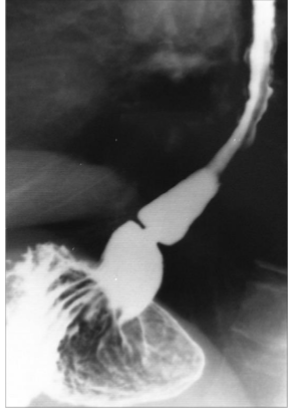

What is this

Zenkers Diverticulum